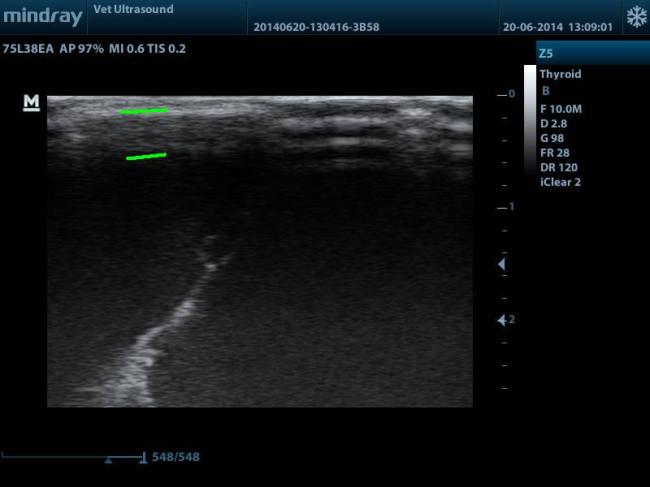

Η ΠΡΩΤΗ ΕΙΚΟΝΑ ΠΟΥ ΠΗΡΑ ΑΠΟ ΤΟΝ ΥΠΕΡΗΧΟ. ΟΙ ΔΥΟ ΠΡΑΣΙΝΕΣ ΓΡΑΜΜΕΣ ΟΡΙΟΘΕΤΟΥΝ ΤΗΝ ΠΕΡΙΟΧΗ ΑΠΟ ΤΟ ΥΠΟΛΟΙΠΟΜΕΝΟ ΕΓΚΕΦΑΛΙΚΟ ΠΑΡΕΓΧΥΜΑ. ΥΠΗΡΧΕ ΟΜΩΣ Η ΥΠΟΨΙΑ ΥΔΡΑΝΕΓΚΕΦΑΛΙΑΣ.